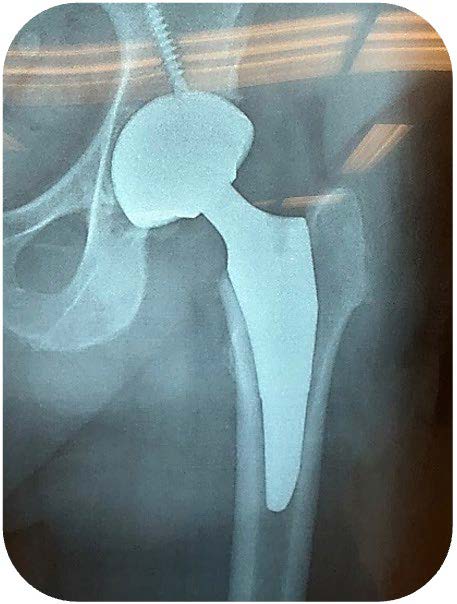

Libertas® Mini TR Stem

Short Stem. Stable Fixation. Designed for Today’s Hip Reconstruction.

The Libertas Mini TR Stem is a tapered, uncemented femoral stem engineered to deliver predictable initial stability with a reduced stem length and distal reduction geometry. It is designed to support efficient femoral preparation and insertion across surgical approaches, including the direct anterior approach.

• Reduced stem length — approximately 37 mm shorter than the standard Libertas TR stem